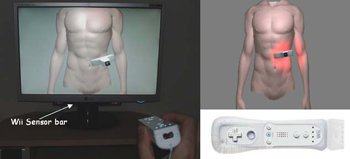

Purpose: We present here a simulator for interventional radiology focusing on percutaneous transhepatic cholangiography (PTC). This procedure consists of inserting a needle into the biliary tree using fluoroscopy for guidance. Methods: The requirements of the simulator have been driven by a task analysis. The three main components have been identified: the respiration, the real-time X-ray display (fluoroscopy) and the haptic rendering (sense of touch). The framework for modelling the respiratory motion is based on kinematics laws and on the Chainmail algorithm. The fluoroscopic simulation is performed on the graphic card and makes use of the Beer-Lambert law to compute the X-ray attenuation. Finally, the haptic rendering is integrated to the virtual environment and takes into account the soft-tissue reaction force feedback and maintenance of the initial direction of the needle during the insertion. Results: Five training scenarios have been created using patient-specific data. Each of these provides the user with variable breathing behaviour, fluoroscopic display tuneable to any device parameters and needle force feedback. Conclusions A detailed task analysis has been used to design and build the PTC simulator described in this paper. The simulator includes real-time respiratory motion with two independent parameters (rib kinematics and diaphragm action), on-line fluoroscopy implemented on the Graphics Processing Unit and haptic feedback to feel the soft-tissue behaviour of the organs during the needle insertion. Keywords: Interventional radiology; Virtual environments; Respiration simulation; X-ray simulation; Needle puncture; Haptics; Task analysis |

L. ap Cynydd, N. W. John, F. P. Vidal, D. A. Gould, E. Joekes, and

This paper reports on a low cost system for training ultrasound imaging techniques. The need for such training is particularly acute in developing countries where typically ultrasound scanners remain idle due to the lack of experienced sonographers. The system described below is aimed at a PC platform but uses interface components from the Nintendo Wii games console. The training software is being designed to support a variety of patient case studies, and also supports remote tutoring over the internet. Keywords: Ultrasound Training, medical virtual environment, hci |